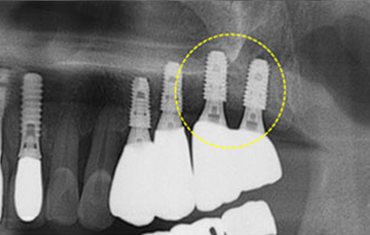

타 치과의 뼈 이식 후 골조직

램브란트치과 상인점 뼈이식 후 골조직